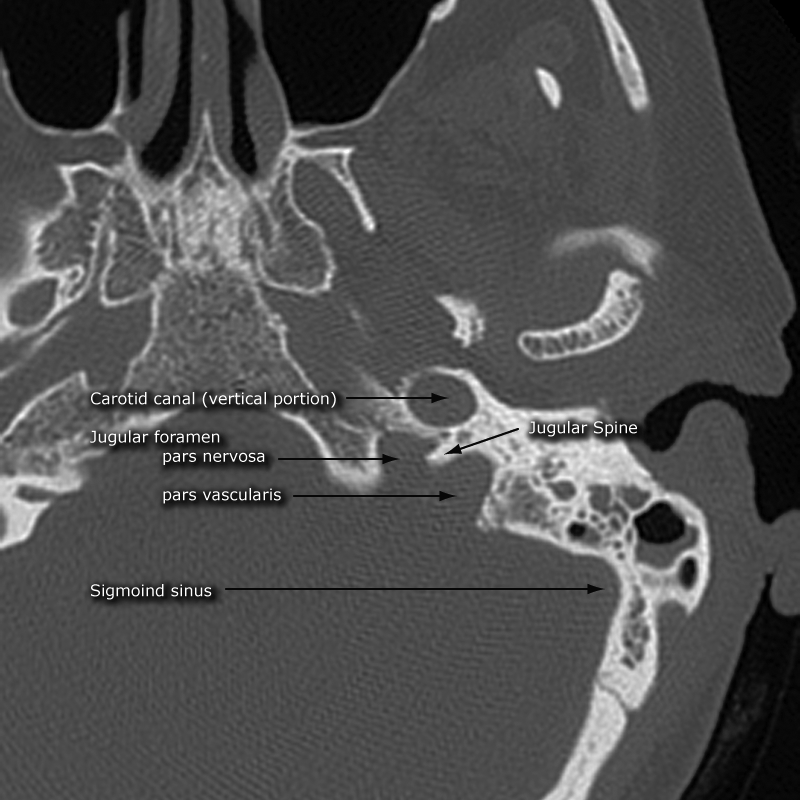

Jugular Foramen

• Divided into two separate pars via the jugular spine

• Pars Nervosa

• Anterio-medial

• Transmits CN 9

• Pars Vascularis

• Posterio-lateral

• Transmits CN 10 + CN 11 + Jugular vein

• Jugular foramen picture - Case courtesy of Frank Gaillard, Radiopaedia.org, rID: 35926